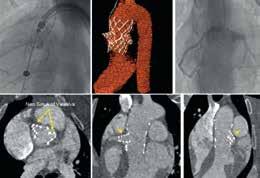

Elimination of Hemodynamic Changes During Ex Vivo Lung Perfusion Improves Dynamic Compliance

Ex vivo lung perfusion (EVLP) involves ventilating and perfusing lungs outside of the body, allowing for longer preservation, evaluation of lung function, and treatment of donor organs. Standard EVLP protocols have either utilized 100% of calculated cardiac output (CO) (ex. Lund Protocol) or lower CO targets between 30-50% (ex. Toronto Protocol).

High CO targets have been associated with increased edema formation while low flow protocols have largely resulted in lung failure. Our center’s established EVLP protocol involves perfusion of lungs

during EVLP at 30% cardiac output with evaluations performed every three hours at 50% of cardiac output. It is unclear if this increase in cardiac output improves V/Q mismatch, or if it is deleterious to the lungs. In this study, we compared our standard negative pressure ventilation EVLP protocol with evaluations performed at 50% cardiac output to a modified protocol without an increase in cardiac output during evaluations.

The perfusate used during EVLP was comprised of common hospital ingredient perfusate (CHIP) and autologous packed red blood cells with Piperacillin-Tazobactam (3.375 g), heparin (10,000 IU), and methylprednisolone (500mg). Lung protective ventilation was employed with tidal volumes of 6-8 mL/kg, a respiratory rate of 6-8 bpm, PEEP of 5-8 cmH2O, and an FiO2 of 21%.

Every three hours, an evaluation was performed. The standard/control protocol involves increasing flow from 30% to 50% CO and applying mixed sweep gas through the de-oxygenator for five minutes during evaluations. The experimental protocol only applies the mixed sweep gas with CO

We developed 27 models using three ML algorithms: gradient boosting decision tree (GBDT), random survival forests (RSF), and Cox regression, combined with radiomic and clinical features (preoperative complications, T stage, hemoglobin, and AST). The optimal model, a GBDT integrating dual-region radiomics and clinical features, outperformed all others. It achieved an integrated area under the curve (iAUC) of 0.854 and an integrated Brier score (iBS) of 0.160, indicating strong discrimination and calibration. For timespecific predictions, its 1-year time-dependent AUC (tAUC) was 0.712 (95% CI 0.655–0.738), and 3-year tAUC was 0.733 (95% CI 0.655–0.805). Importantly, it effectively stratified patients into high- and low-risk groups (P < 0.001), a critical tool for personalized risk assessment.

maintained at 30%. Standard lung performance characteristics were regularly assessed, including PF ratio, pulmonary vascular resistance (PVR), dynamic compliance, minute ventilation, and percentage lung weight-gain. Dynamic compliance was significantly improved in the experimental group that did not receive higher flows during evaluations. The control group’s dynamic compliance decreased after each subsequent evaluation after six hours. Similarly, minute ventilation was significantly higher in the experimental group compared to the

control group.

Other measures, including PVR, pulmonary artery pressures, PF ratio, and lung weight gain (72.7% weight gain for the control group, 77.1% for the experimental group), were not significantly different between groups. While lactate did not differ significantly between groups, lactate did climb more rapidly in the control group compared to the experimental group, which was performed without higher cardiac output evaluations.

Higher cardiac output targets have been associated with increased rates of edema formation, while low flow protocols have largely resulted in

early lung failure. Moderate flow perfusion targeting a CO between 20-40% of predicted CO has generally allowed for stable, prolonged EVLP. Despite their limited duration, temporary increases in CO during evaluations result in lung injury, impairing dynamic compliance, ventilation, and increasing lactate formation over 12 hours compared to a consistent CO of 30%. Modification of future protocols to eliminate hemodynamic modifications with higher CO may help to further prolong EVLP duration by reducing lung injury and improving ventilation.

Figure 1. Central image of the study.

Ryaan EL-Andari University of Alberta, Alberta, Canada